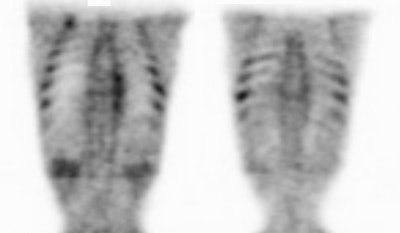

|

Marrow activity: The images below are from two separate patients each showing mild FDG accumulation within the vertebral bodies. |

|

|

|

Growth colony effect: The patient shown below had received growth colony stimulating factor (GCSF). Note the extensive increased marrow activity. Note increased splenic activity also seen as a result of GCSF therapy. Click image to view rotating avi file. |

|

|